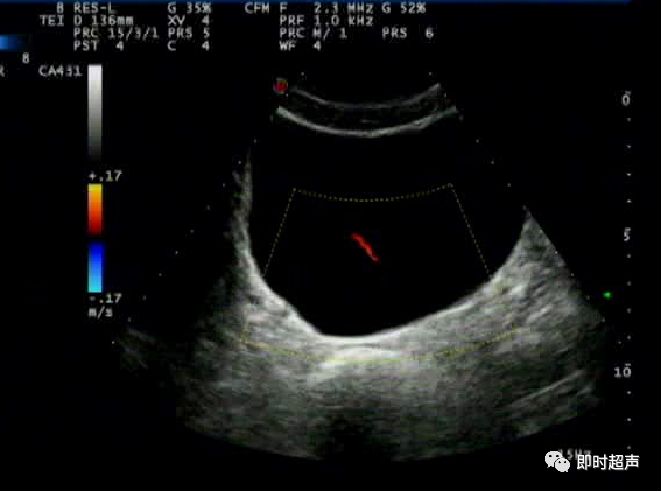

- CDFI:显示肿瘤基底部有细条状血流彩色Doppler频谱显示有动脉频谱:RI>0.60

左图:菜花样团状中、强回声(箭头)

右图:CDFI显示显示肿瘤基底部有细条状血流 (箭头)

膀胱壁实性占位

二维 CDFI